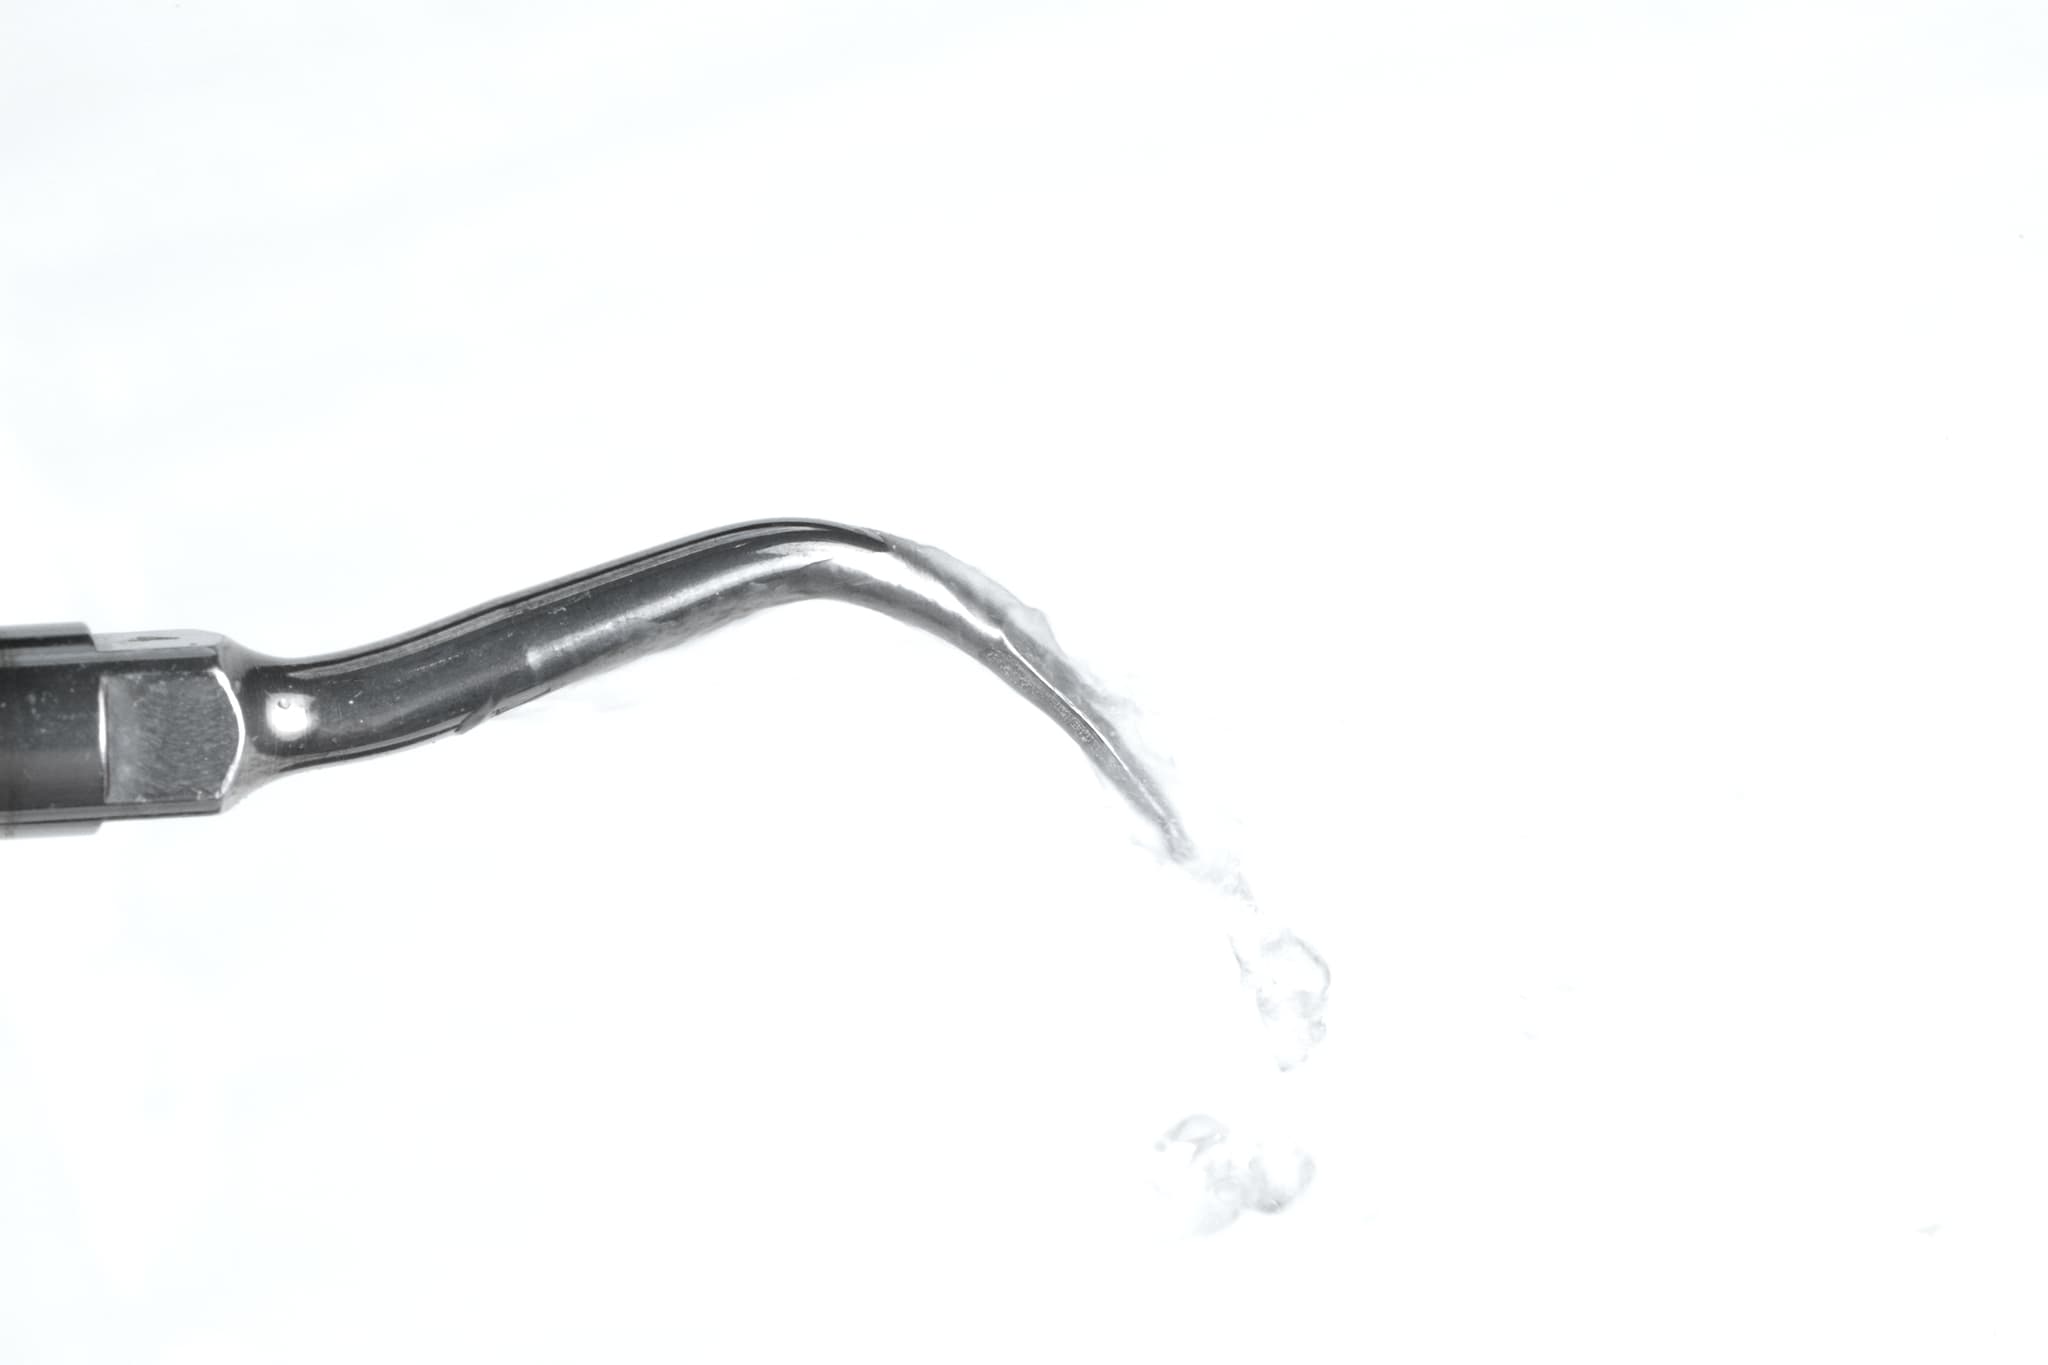

2. Active Periodontal Therapy

Minimally invasive. Precisely delivered.

Depending on severity, treatment may involve non-surgical scaling and root planing, laser-assisted therapy, or targeted antimicrobial treatments. We work flaplessly where possible, focusing on cleaning the root surface and halting progression—without unnecessary trauma.